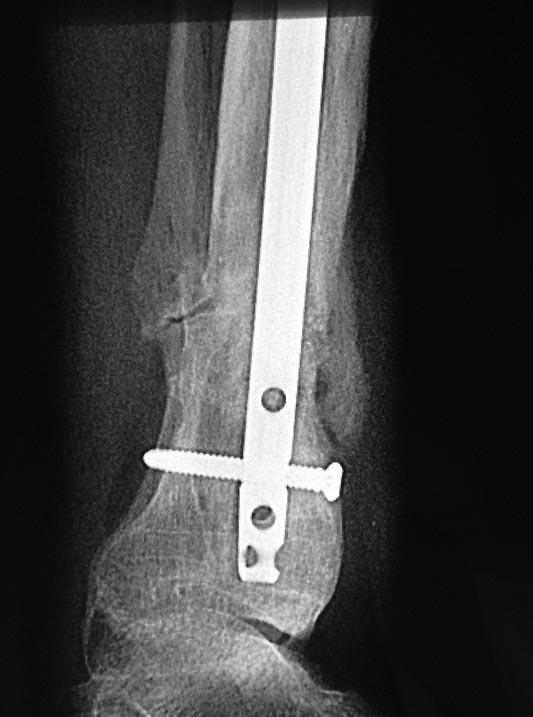

Уважаемые коллеги выразите Ваше мнение по следующему случаю. Молодой

человек, 27 лет, находится на лечении с диагнозом: Ложный сустав

большеберцовой кости в нижней трети, фиксированный интрамедуллярным

блокированным стержнем (12.02.2014 г), ложный сустав малоберцовой кости

в нижней трети левой голени, посттравматический артроз левого

голеностопного сустава 1 стадии. Укорочение левой нижней конечности на

В феврале 2014 г выполнил первым этапом: Фиксацию ложного

сустава в АНФ с восстановлением осей сегментов. Через семь дней БИОС с

рассверливанием.

После операции - вальгус голеностопного сустава. Гладкое течение

послеоперационного периода. Нагрузка по переносимости боли. Через 6

недель динамизация, через 2 недели стали мигрировать 2 фронтальных

винта. Пытался подкрутить, пришлось удалить.

Через 6 мес. контроль - линия ложного сустава прослеживается, но имеется

периостальная костная мозоль.

Не хватает стабильности.